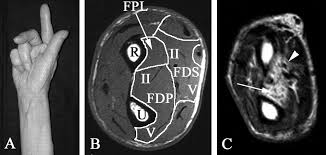

Touch small finger to the thumb so the nails are parallel pinch paper between thumb and radial side of index finger in the first webspace flex mcp and straighten pip Ericson's test is a clinical maneuver for assessing the strength of the fdp and fpl muscles in anterior interosseous nerve syndrome, and other proximal entrapments of the median nerve. The neurosurgeon is notified, and additional imaging is ordered. In supine, the ability to lift the head and neck against gravity for an extended period. Flexor pollicis longus (fpl) instruct the patient bend the tip of your thumb insertion: Jull, pt, phd,a shaun p. The other hand is used to give resistance with the thumb placed over the dorsal surface of the distal phalanges of toes. How to test lower abdominal strength updated this test involves the lower fibers of the rectus abdominals (attached to the pubic crest and symphysis). The tendons are thus crucial for both the architecture and the biomechanics of the musculoskeletal system. For more detail, go for this link wrist and hand examination hand examination; About press copyright contact us creators advertise developers terms privacy policy & safety how youtube works test new features press copyright contact us creators. Fds, fdp, fpl, epl testing. Distal phalanxes of fingers action:

Observe the dip joints as the patient pulls at end range flexion. O following repair or reconstruction of an fdp tendon the tension must be identical to the other fdps, since the excursion of the combined tendons is equal to the shortest tendon. How to test lower abdominal strength updated this test involves the lower fibers of the rectus abdominals (attached to the pubic crest and symphysis). The test for lumbrical muscle tightness must elicit the active recruitment of the fdp: 14 of these are tested bilaterally. O when testing for fds the fdp is defunctioned because the fdp tendons are combined, while the fds muscles are separate in the forearm. Active flexion is required to see the dip joint paradoxical extension. The flexor digitorum profundus is a muscle in the forearm of humans that flexes the fingers (also known as digits).

How to test lower abdominal strength updated this test involves the lower fibers of the rectus abdominals (attached to the pubic crest and symphysis). The neurosurgeon is notified, and additional imaging is ordered. In supine, the ability to lift the head and neck against gravity for an extended period. The other hand is used to give resistance with the thumb placed over the dorsal surface of the distal phalanges of toes. Distal phalanxes of fingers action: Since fdp is the major muscle for hand gripping power, dynamometer (handgrip ergometer) can be used for measuring the hand gripping strength. To test the flexor digitorum longus muscle, you want to eliminate the effects of other muscles and this is fortunately easy to do as it is the only muscle that plantarflexes the distal phalanges of the toes. The flexor endurance test is the first in the battery of three tests that assesses muscular endurance of the deep core muscles (i.e., transverse abdominis, quadratus lumborum, and erector spinae). Falla, pt, phdc abstract background: Other fingers should be stabilized in extension instruction: The hip flexors are several muscles that bring your legs and trunk together in a flexion movement. The flexor digitorum profundus is a muscle in the forearm of humans that flexes the fingers (also known as digits). All the lesser toes should curl at the same time because the one muscle belly pulls on the tendon.

It is essential that a grade of 3 be established before proceeding to application of resistance for grades above 3 or to alternate gravity minimized tests for. You can strain or tear your hip flexor muscles through sudden movements or falls. O when testing for fds the fdp is defunctioned because the fdp tendons are combined, while the fds muscles are separate in the forearm. Since fdp is the major muscle for hand gripping power, dynamometer (handgrip ergometer) can be used for measuring the hand gripping strength. The therapist uses one hand to stabilize the metatarsals with the fingers on the plantar surface and the thumb on the dorsum of the foot. How to test lower abdominal strength updated this test involves the lower fibers of the rectus abdominals (attached to the pubic crest and symphysis). Enroll in our online course: She has made gains in all muscles